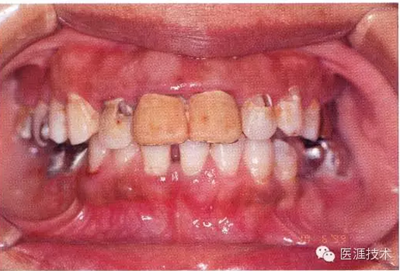

44歲牙周炎女性的臨床照片

44歲患有糖尿病病史(未治愈)。菌斑控制不良。通過牙周探診,全頜有4~8mm的牙周袋,在X光片中可以看到上頜前牙處中度牙槽骨吸收,磨牙處重度牙槽骨吸收。二次齲齒和根面齲齒也有發(fā)生??梢钥吹礁∧[性腫脹,收到刺激后會出血。